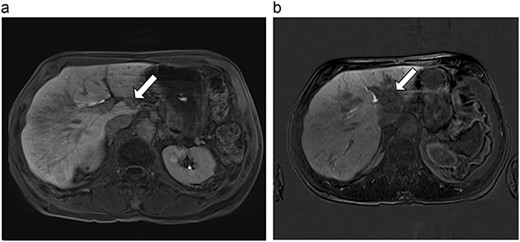

| 2 (4a,b) | 67, M | Colon adenocarcinoma | 8 cycles capecitabine and oxaliplatin | 6 | Laparoscopic microwave ablation | 15 | 35 | 20 | 6 | No |

(a) Pre-ablation MRI demonstrating 15 mm lesion in caudate lobe of liver (image degraded by motion artifact). (b) Post-ablation MRI (20 days postoperatively) demonstrating 35 mm complete ablation of caudate lesion (image degraded by motion artifact).